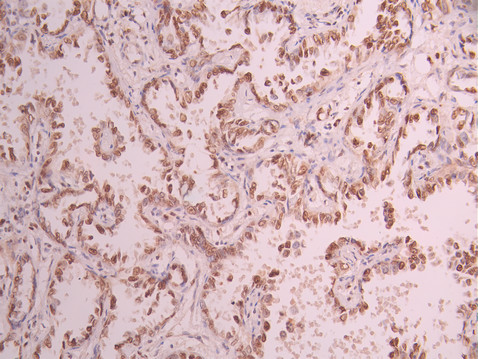

• IHC image of CSB-RA799971A0HU diluted at 1:100 and staining in paraffin-embedded human lung cancer performed on a Leica BondTM system. After dewaxing and hydration, antigen retrieval was mediated by high pressure in a citrate buffer (pH 6.0). Section was blocked with 10% normal goat serum 30min at RT. Then primary antibody (1% BSA) was incubated at 4°C overnight. The primary is detected by a Goat anti-rabbit polymer IgG labeled by HRP and visualized using 0.05% DAB.